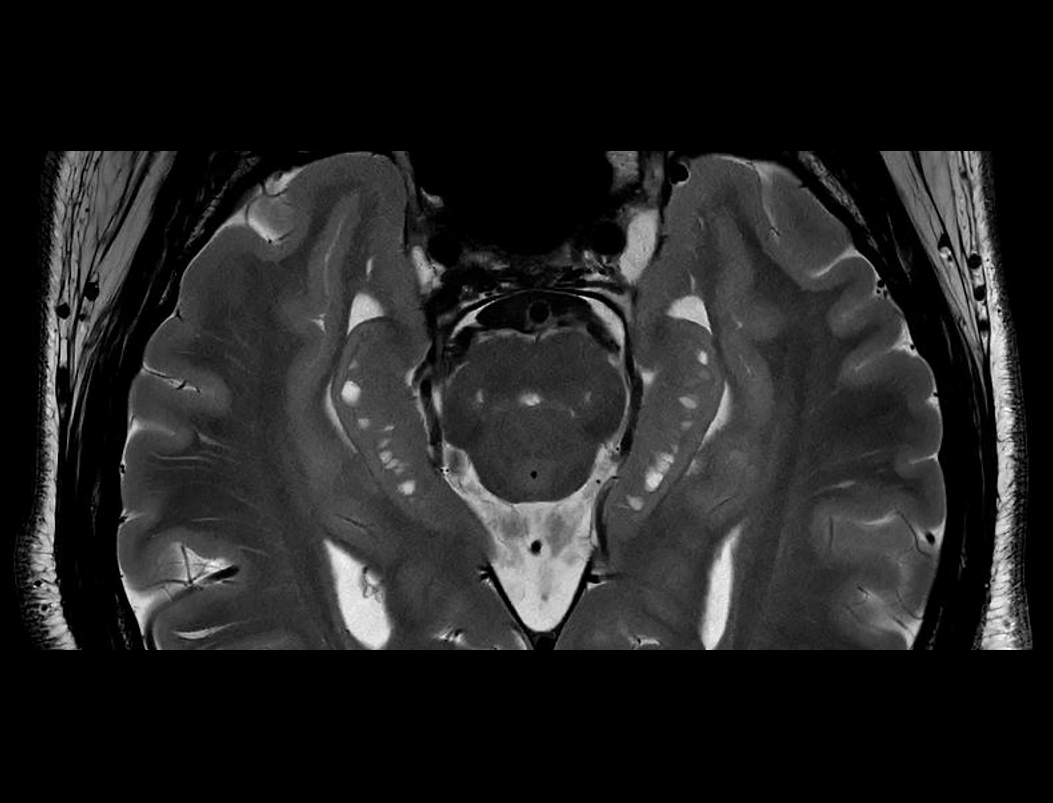

Boundless Clinical Scenarios

ACS (AI-assisted Compressed Sensing)는 United Imaging의 독점 MR 가속 솔루션으로 속도와 이미지 품질을 최적으로 균형있게 조화시키는 데 사용됩니다. CS, HF, PI를 결합하고 최첨단 딥러닝 신경망을 AI 모듈로 혁신적으로 도입하여 재구성 절차에 적용합니다. 이를 통해 사용자는 영상 품질을 향상시키면서도 검사 시간을 늘리지 않거나 이미지 품질을 저하하지 않고 검사 시간을 단축시킬 수 있습니다. 이는 더 완벽한 검사를 가능하게 하며, 영상의학과 전문의들의 진단가치를 높이고 환자의 편안함을 향상시킵니다.

MRI 영상에서 더 높은 가속 수준을 실현.

각 부위의 획득 시간을 100초 이내로 단축하여, 환자 처리량을 크게 향상시키고 움직임에 인한 아티팩트를 줄입니다.

작은 해부학적 구조물을 더욱 정확하게 묘사하여 진단 능력을 확장시킵니다.